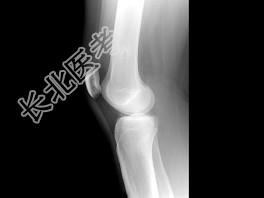

- 单项选择题女,39岁。发现左大腿下段后部有一肿块, 质较硬,无明显疼痛感觉, 结合所提供的图像,最可能的诊断是 ( )

A、软骨肉瘤

B、软骨瘤

C、骨肉瘤

D、骨软骨瘤

E、骨瘤